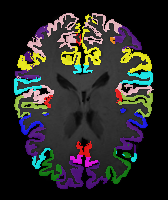

Image Manual Seg DA-1 Mono-21 DA-21 Mono-65 Refer to caption Refer to caption Refer to caption Refer to caption Refer to caption Refer to caption

Figure 2:  Examples of knee MRI registration (top) and brain MRI segmentation (bottom) results. Top: The first two columns are the moving image/segmentation and the target image/segmentation followed by the warped moving images (with deformation grids)/segmentations by different models. Bottom left to right: original image, manual segmentation, and predictions of various models. Mono-i𝑖i and DA-i𝑖i represent the mono- and DA models with i𝑖i manual segmentations respectively.

Results: All trained networks are evaluated using Dice overlap scores between predictions and the manual segmentations for the segmentation network, or between the warped moving segmentations and the target segmentations for the registration network. Tabs. 1 and 2 show results for the knee and brain MRI experiments respectively in Dice scores (%). Fig. 2 shows examples of knee MRI registrations and brain MRI segmentations.

Brain results: Dice scores for segmentation and registration increase by about 2.6 and 3.5 respectively for the cortical structures of the brain MRIs.

Qualitative results: DA achieves more anatomically consistent registrations than the mono-networks on the knee (Fig. 2) and Brain MRI samples (see supplementary material).

Moving Target Mono-0 Mono-21 DA-1 DA-21 Mono-65 Refer to caption Refer to caption Refer to caption Refer to caption Refer to caption Refer to caption Refer to caption Refer to caption Refer to caption Refer to caption Refer to caption Refer to caption Refer to caption Refer to caption